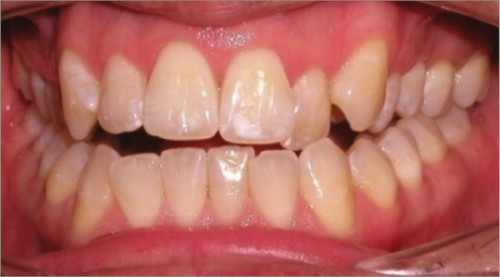

30 year old male:

Diagnosis:

- Upper and lower crowding

- Narrow upper & lowerarch forms

- Open bite

Treatment:

- Invisalign

- Non-Extraction

- 27 months